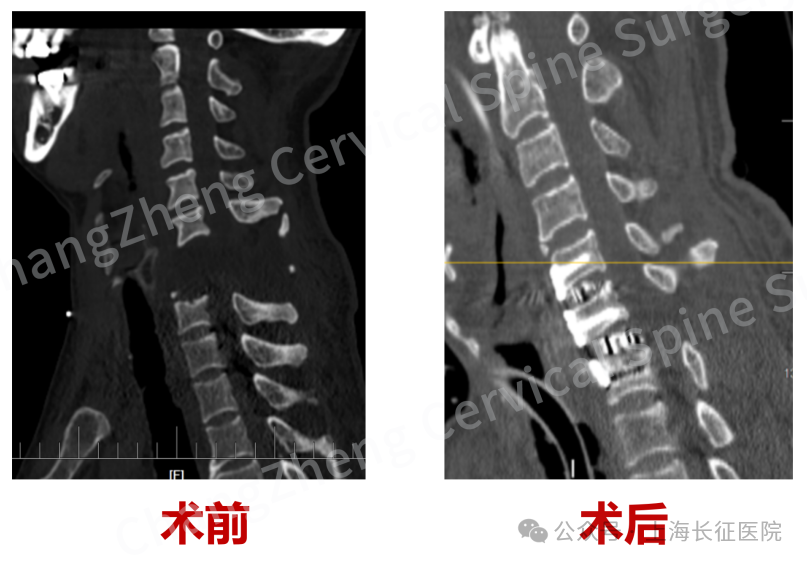

眼前这位患者,几乎已被宣判“死刑”。影像学检查显示,患者发生了罕见的大跨度颈椎离断式脱位,脊髓严重挫伤、关键的神经血管结构撕裂。

影像检查显示患者颈椎罕见大跨度脱落

当时,患者因颈部遭受机械臂重击,导致颈椎瞬间遭受毁灭性损伤,当场高位截瘫、心跳骤停,经紧急心肺复苏才勉强恢复微弱生命体征。影像学检查结果令人震惊:颈椎发生极其罕见的大跨度脱位,其严重程度犹如“身首离断”,已造成脊髓严重挫伤、关键神经血管结构撕裂。

术前、术后影像对比,手术效果良好